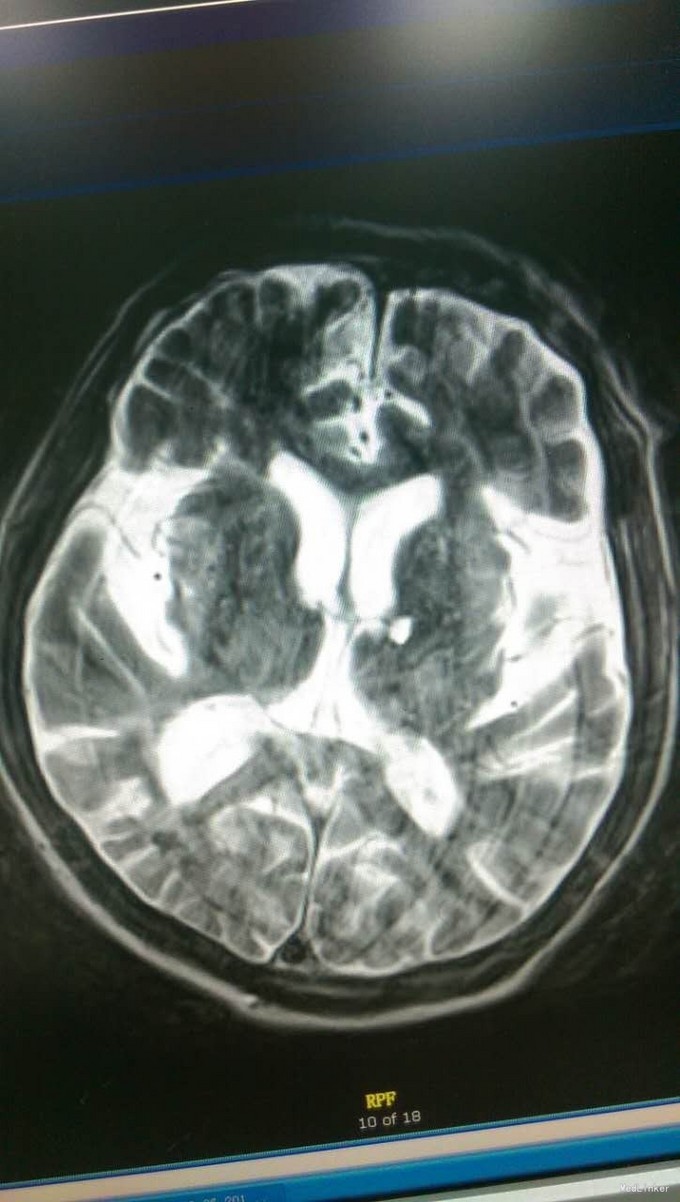

体格检查:T:36.2℃,P:79次/分,R:16次/分,BP:108/60mmHg。皮肤巩膜无黄染,无瘀点瘀斑。浅表未触及肿大淋巴结,肺部听诊双肺呼吸音清,未闻及干湿啰音,心律齐,各瓣膜听诊区未闻及病理性杂音,腹软,无压痛,肝脾肋下未触及,双下肢无浮肿,足背动脉博东良好。 专科查体:神志清醒,查体欠合作,言语正常,发音构音不良。双瞳孔等大正圆,D≈3.0mm,光反应灵敏。双眼向各方向运动充分,无眼震。无面舌瘫。颈强阴性。四肢肌力V级,四肢肌张力正常。BCR(L:++,R:++),TCR(L:++,R:++),PSR(L:++,R:++),ASR(L:++,R:++)。Babinski征(L:±,R:±)。深浅感觉查体未见确切异常。共济运动双侧稳准。 辅助检查:头CT(我院门诊,11-23)脑内多发软化灶。老年性脑萎缩。颈后部皮下血肿

初步诊断:血管性认知功能障碍 脑梗塞后遗症 高血压3级(极高危险组)2型糖尿病 冠心病 诊断依据:1、患者既往多发脑梗塞病史;此次以”糊涂5个月,加重半月余“为主诉入院,血管性认知功能障碍2、患者5个月前患脑梗塞,当时右侧肢体活动不灵,遗留言语含糊。3、高血压病史10余年,最高可达180/90mmHg,口服美卡素80mg日一次控制在130-140/70-80mmHg。4、2型糖尿病10余年,拜糖平50mg日3次、格华止0.5g日3次餐中口服,近半年停用诺和灵30R皮下注射,控制不详。5、冠心病10余年,偶有心前区疼痛、胸闷发作,平日口服扩冠。 治疗计划:1、完善入院常规检查如血常规、血生化、头MRI+DWI及血管相关检查等 2、给予患者改善脑循环、抗血小板、营养脑神经、改善认知功能、营养心肌、控制血压、监测血糖等对症支持治疗。